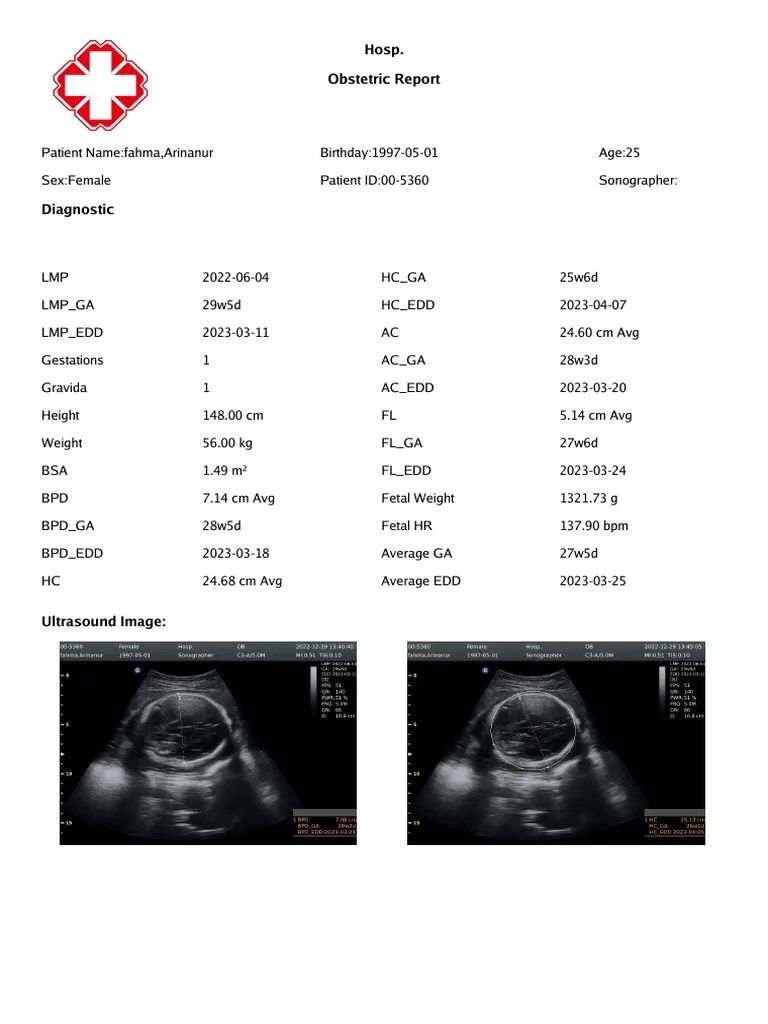

Usreport005360 Obstetric Report PDF How To Read Obstetric Report Should ultrasound images be stored? How to read a ctg. Reading ultrasound reports becomes easier when one is familiar with common abbreviations used in obstetrics and gynecology. Gtpal is an acronym to remember essential information for a complete obstetric history. Each letter represents one aspect of the obstetric history that should be. List 3 things to be included in an. How To Read Obstetric Report.